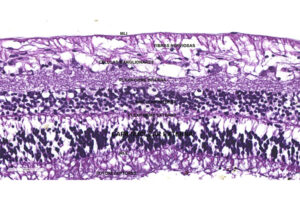

Globo ocular de embrión de 9-10 semanas de desarrollo

La capa pigmentada (epitelio pigmentado de la retina – EPR) y la capa sensorial que consta de nueve capas: capa de fotoreceptores, membrana limitante externa, capa nuclear externa, capa plexiforme

El epitelio pigmentado es una capa que consta de una hilera de células hexagonales de tamaño uniforme (16 μ de diámetro) y disposición regular. Las células tienen un núcleo redondo

La capa de conos y bastones tiene una disposición en empalizada de sus elementos, los bastones son delgados cilíndricos, su longitud corresponde al grosor de toda la capa y están

La membrana limitante externa está constituida por uniones tipo zónula adherente entre los fotoreceptores y las prolongaciones de las células de Müller.

La capa nuclear externa está formada por ocho o nueve capas de células con núcleo densamente teñido. Según la morfología nuclear podemos distinguir dos tipos de células: una más pequeña

La capa plexiforme externa está formada por fibras que se encuentran laxamente dispuestas: los axones de los bastones y conos y las dendritas de las células bipolares y horizontales; en

La capa nuclear interna es una masa de células muy juntas que semeja la nuclear externa pero más fina; tiene tres tipos de neuronas, las células bipolares cuyas dendritas entran

La capa plexiforme interna está formada por un fino retículo de fibras en donde se encuentran las sinapsis de las células bipolares, con las células amacrinas y ganglionares.